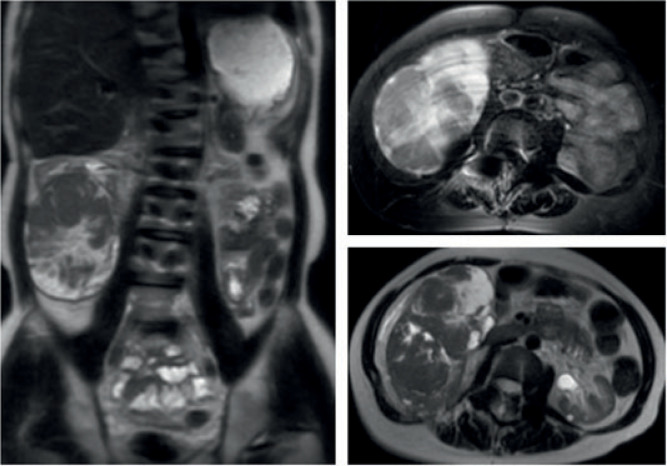

Although rare in adults, Wilms tumor is the most common pediatric renal tumor. Treatment typically involves radical nephrectomy followed by adjuvant chemotherapy or radiation, although outcomes differ between children and adults which may be due to challenges in accurately diagnosing these patients. In this article, we present a case report of an adult patient with Jeune syndrome and multiple urologic abnormalities who underwent radical nephrectomy for a large renal mass and was subsequently diagnosed with an epithelial predominant Wilms tumor. Epithelial predominant Wilms tumor may have distinct origins from other Wilms tumor histological subtypes and may incur better outcomes. Herein, we discuss the literature surrounding this rare entity as well as the anticipated treatment course.